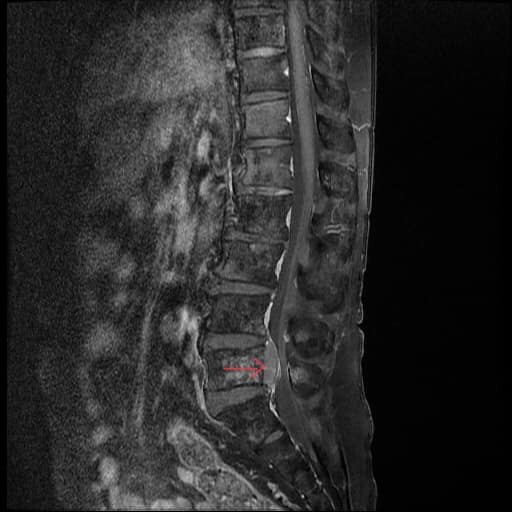

Hình ảnh khối u chèn ép tủy sống trên phim MRI của bệnh nhân. Ảnh: BVCC

Sau khi nhập viện điều trị, bệnh nhân được các bác sỹ thăm khám và chỉ định chụp MRI cột sống phát hiện khối u tủy L5 phát triển từ khối di căn cột sống gây choán chỗ, hẹp nặng ống sống và chèn ép các cấu trúc thần kinh.